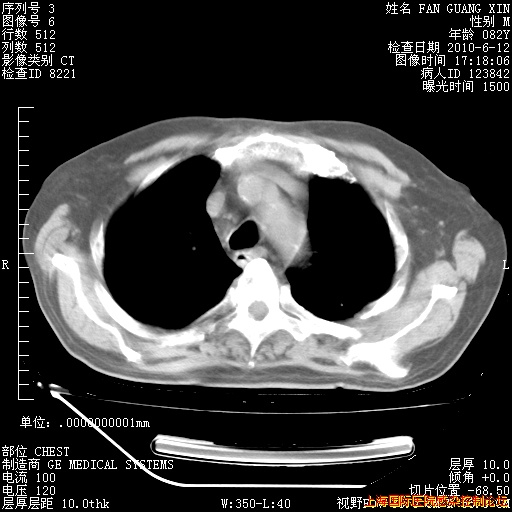

6月12日纵膈窗